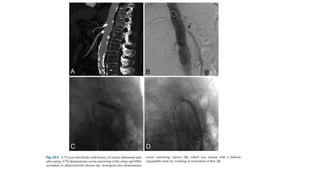

• Endovascular procedurestreat two of the most lethal complications of acute aortic dissection, false lumen rupture and malperfusion syndrome. • Thoracic endovascular aortic repair (TEVAR), fenestration with or without stenting, or a combination is employed in these patients. • The guiding principle of endovascular treatment is to define the anatomy of the dissection, the location of the entry tear with respect to nearby critical vessels, and the mechanism (static or dynamic) of arterial obstruction.

• 59.

• When thearterial anatomy prohibits deployment of a stent graft, or when malperfusion persists despite coverage of the entry tear, fenestration or stenting (or both) can treat the recalcitrant branch vessel obstruction in a targeted, piecemeal fashion. • The goal of the fenestration is to create a large, controlled tear in the dissection flap separating the true and false lumens, allowing blood flow and pressure equilibration across the flap to reperfuse branches of the true lumen that have been excluded by the dissection

• 62.